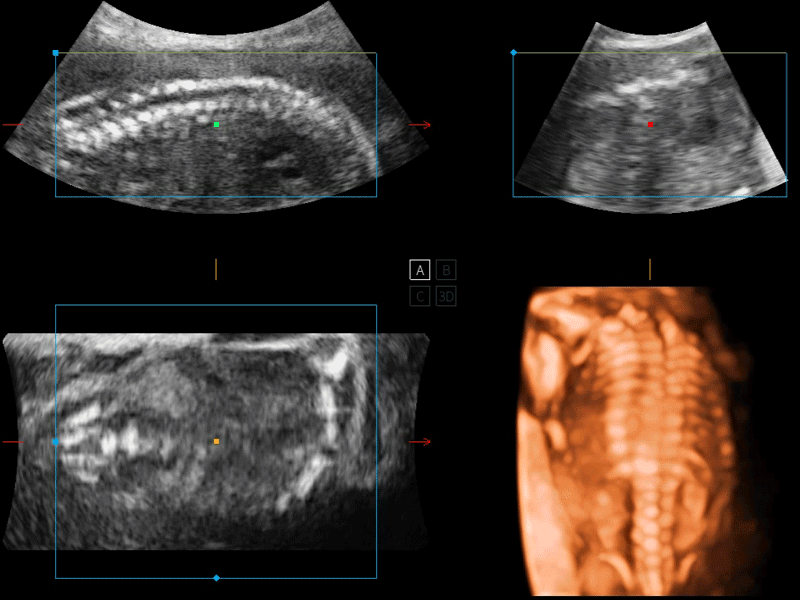

開立醫(yī)療通過不斷的技術(shù)創(chuàng)新,為大眾的生命健康提供持續(xù)關(guān)愛。P12 Plus采用全新一代超聲成像平臺(tái),新平臺(tái)旨在將真實(shí)還原組織解剖結(jié)構(gòu)作為首要目標(biāo)。平臺(tái)采用全新集成化硬件模塊,搭載新一代芯片,系統(tǒng)性能得到大幅提升,為您的診斷提供了豐富的臨床信息。優(yōu)異的圖像表現(xiàn),豐富的探頭配置,全面的應(yīng)用功能,為您日常診斷提供了可靠的助手。